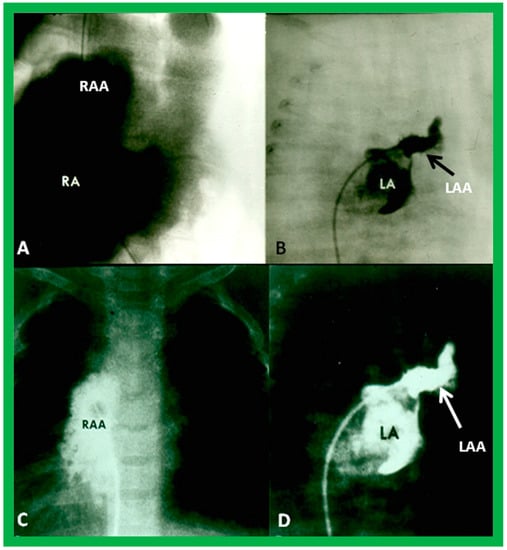

Atrial morphology may be assessed by transesophageal echocardiography (TEE), selective atrial angiography, or by surgical inspection. If these procedures are performed for some other reason, such data may be used to determine the atrial situs. The atrial appendages have characteristic shapes in that the RA appendage is large and broad, while the LA appendage is narrow, tubular, and small. If TEE, selective atrial angiography (Figure 29), or surgical inspection is undertaken for any other reason, securing such data at that time is helpful in evaluating the atrial situs.

Figure 29. Angiographic images of right (RA) (A,C) and left (LA) (B,D) atria in a posteroanterior view illustrating the atrial appendage morphology. The RA appendage (RAA) has a broad, large, and pyramidal shape (A,C), whereas the LA appendage (LAA) has a narrow, small, and tubular shape (B,D). Reproduced from reference [4].